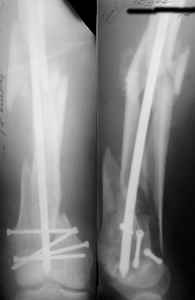

KEMMD> B. Fixation loosening: distal cutting of the nail, non-unions do happen

KEMMD> (cases attached).

The nail can be unlocked in the proximal fragment to prevent it.

KEMMD> Locking Plating has more distal screws than any nail,

In the nails we use now the distal screw is about 3 mm from the nail tip. Many vendors AFAIK in their modern implants moved holes more close to the ends of nails.

KEMMD> fixed angles and

KEMMD> provides much better fixation, especially in osteoporotic bone.